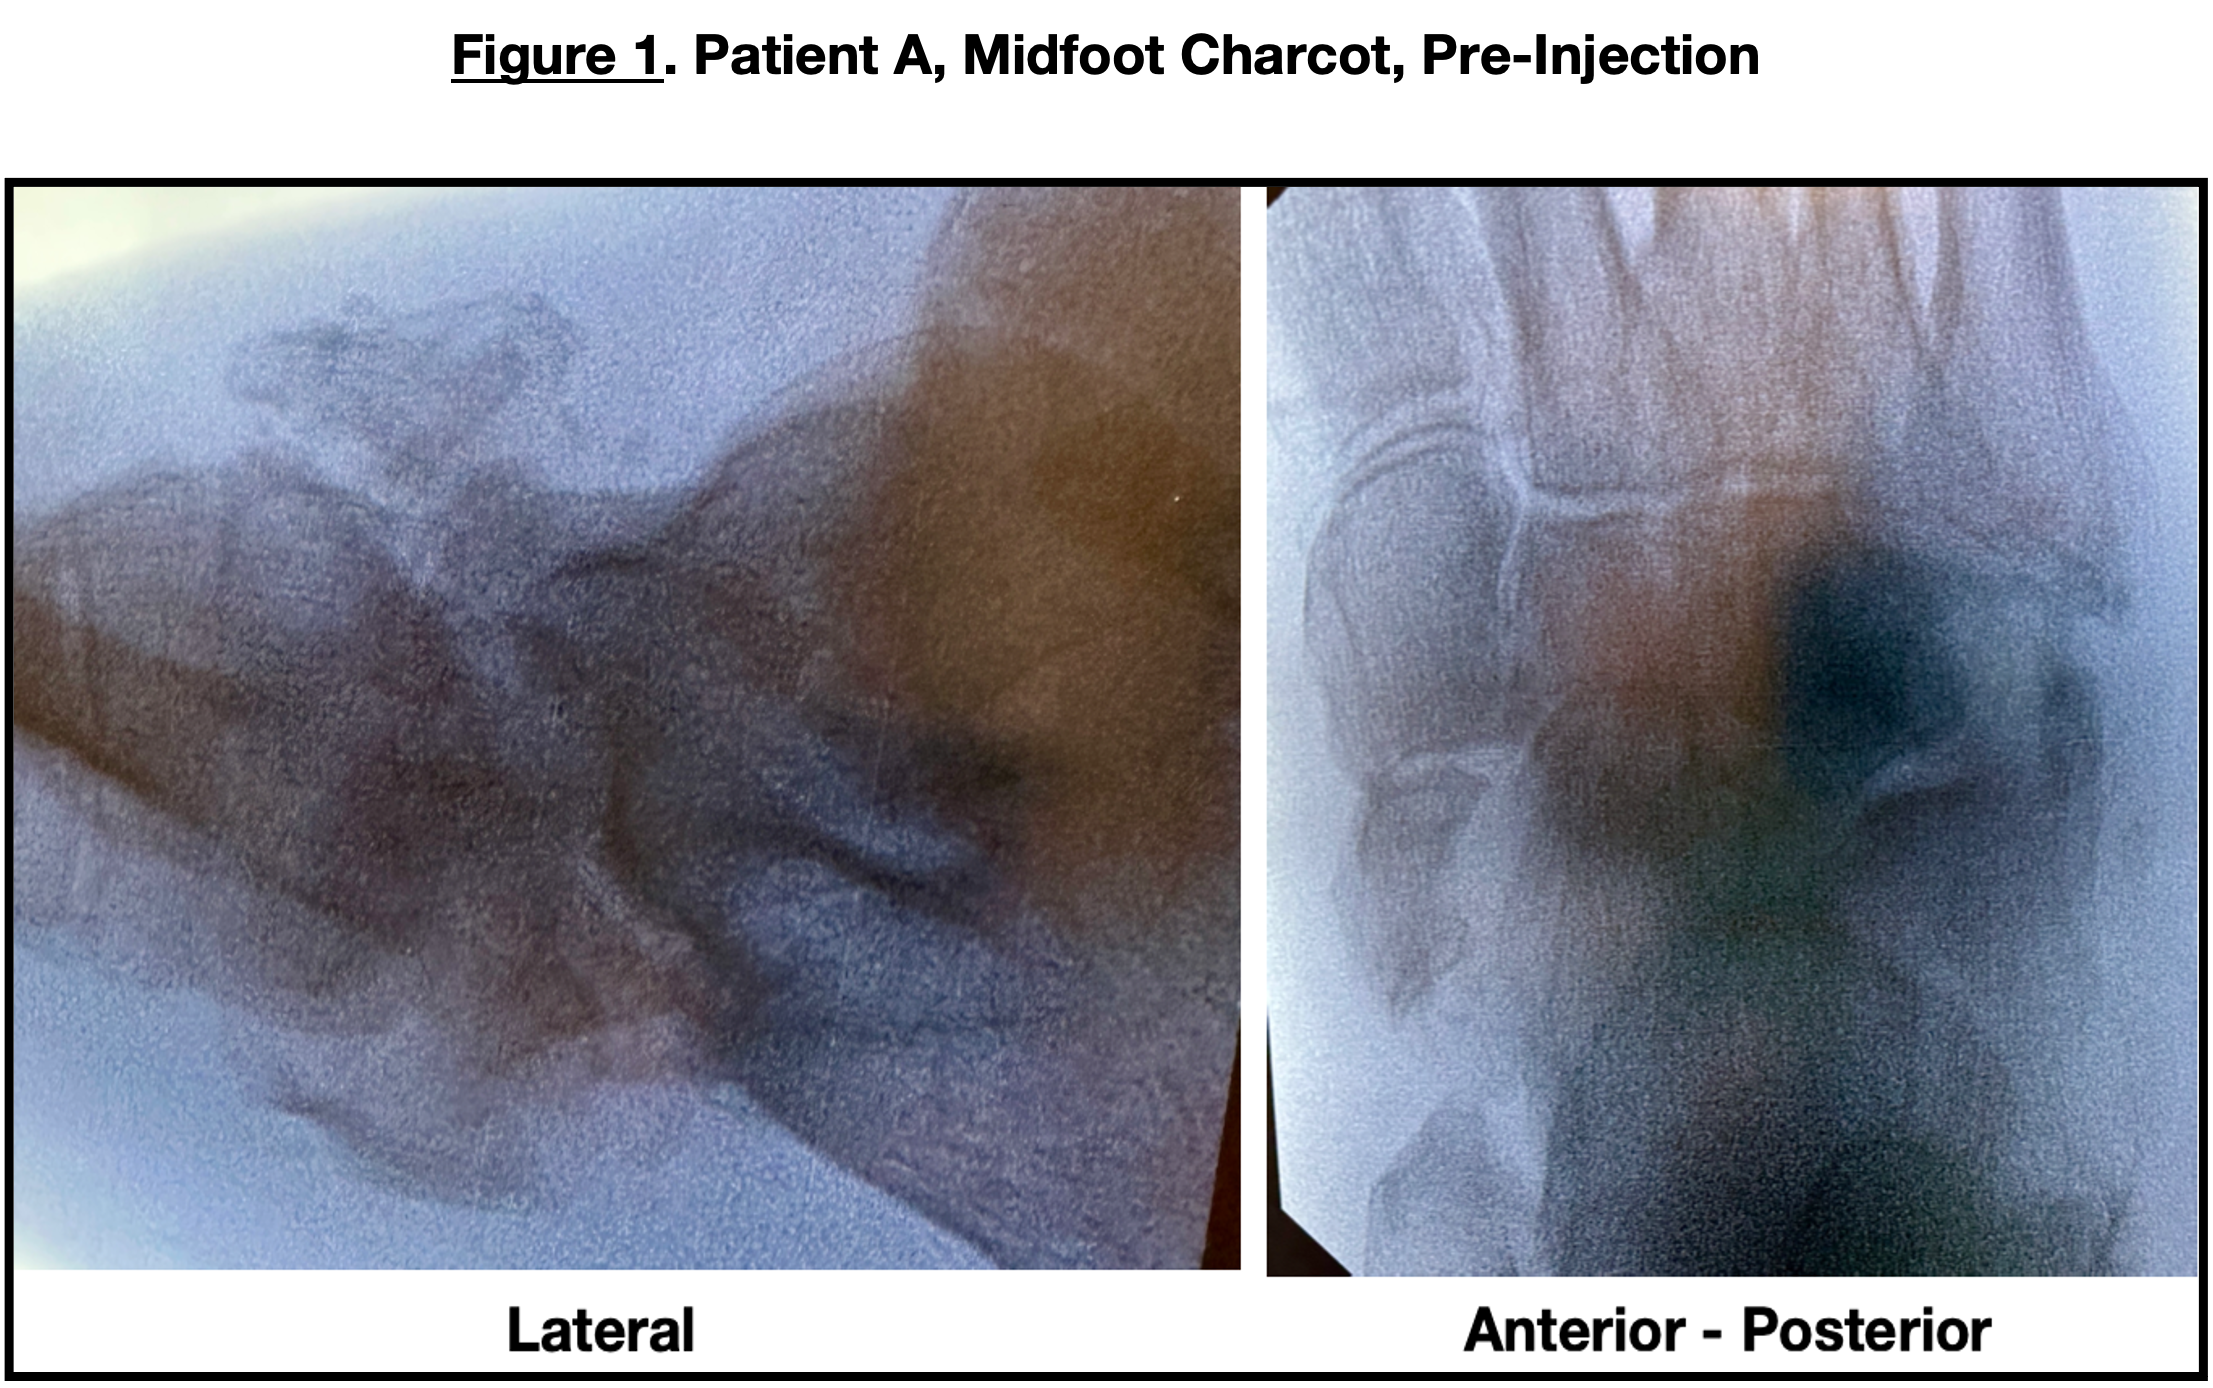

The patient underwent placental tissue injections (Figure 4) into the fracture areas, which were edematous, erythematous, and painful despite having neuropathy. Injections took place percutaneously with the assistance of fluoroscopy (Figure 5) into the anterior calcaneus, calcaneocuboid joint, subtalar joint, and posterior calcaneal body. Administration of these injections used a lateral approach with 2 percutaneous incisions. The patient was seen 2 weeks post-injection, with a significant decrease in erythema, calor, and minimal pain. Her C-reactive protein was 8 mg/dL. Six weeks later, X-rays revealed further calcification and consolidation. She then transferred to appropriate diabetic footwear and began full weight-bearing.